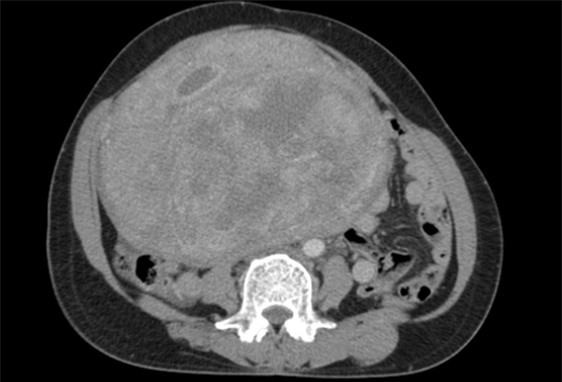

Phim chụp khối u

Qua kiểm tra, các bác sĩ phát hiện trong ổ bụng bệnh nhân có khối u lớn.

Tiên lượng đây là một ca bệnh khó vì khối u rất lớn, chèn ép nhiều cơ quan, cộng thêm thách thức là bệnh nhân bị suy thận, nếu không phẫu thuật kịp thời, nguy cơ bệnh nhân tử vong rất cao. Không còn thời gian chờ đợi, các bác sĩ quyết tâm tiến hành phẫu thuật.

BS Hà chia sẻ, do khối u kích thước lớn làm biến đổi giải phẫu các cấu trúc trong tiểu khung như niệu quản, trực tràng, động mạch chậu 2 bên, mặt khác u lại giàu mạch máu nuôi dưỡng nên nguy cơ chảy máu rất cao nên gây nhiều khó khăn trong việc phẫu thuật.